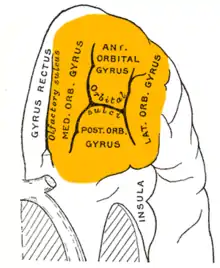

Ubicación aproximada de la COF, en una visión sagital mediante resonancia magnética de imágenes. | ||

Anatómicamente, la COF se define como la parte de la corteza prefrontal que recibe proyecciones desde los núcleos mediales magnocelulares del tálamo mediodorsal.[2] Su nombre se debe a su posición, ya que se encuentra situada inmediatamente sobre las órbitas en las que se ubican los ojos. Se ha hallado una considerable variabilidad individual en la COF, tanto en primates humanos como en no humanos. En los roedores se ha encontrado un área similar.[3]